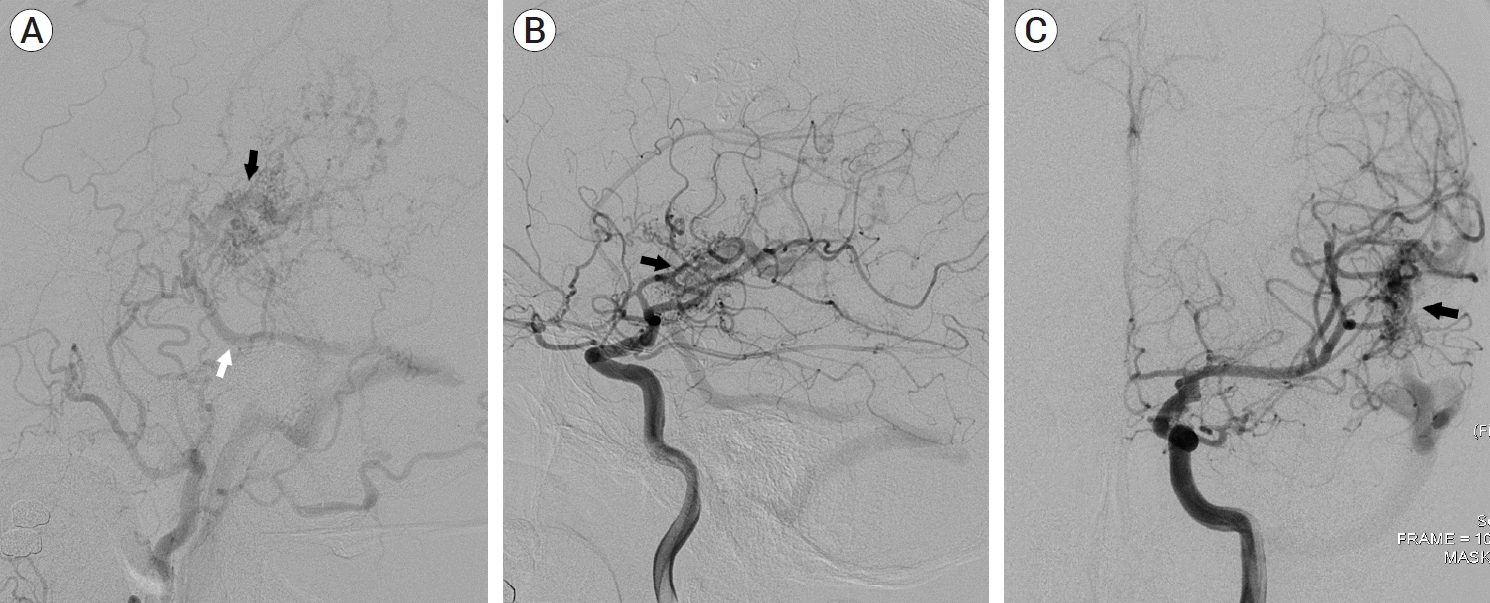

A 39-year-old man visited the neurosurgery department and presented with a left-sided pulsatile headache. The patient had a history of surgical clipping for a ruptured left anterior choroidal artery aneurysm using a conventional pterional approach 2 years previously. Computed tomography (CT) angiography revealed engorged tortuous cortical vessels near the previous craniotomy site and sylvian fissure, indicating a suspicious AVF which had not been detected on CT conducted 2-years before presentation (Fig. 1). Digital subtraction angiography (DSA) was performed for treatment planning, and external carotid angiography demonstrated a dural AVF fed by the branches of the middle meningeal artery (MMA) and superficial temporal artery (STA), draining directly into the engorged superficial middle cerebral vein (SMCV), vein of Labbe, and sigmoid sinus (Fig. 2A). Ectatic changes in the draining veins and cortical venous reflux were observed. Ipsilateral internal carotid artery angiography revealed additional multiple feeders arising from the middle cerebral artery (MCA), suggesting a mixed pial and dural AVF (Fig. 2B, C). Due to the difficulty of the transarterial approach through multiple small feeding arteries, transvenous coil embolization was performed via the sigmoid sinus and enlarged vein of Labbe (Fig. 3). Complete obliteration of the fistula was achieved, confirmed by postoperative DSA (Fig. 4), and the patient was discharged with no neurological complications.

Because of the difference in etiology between pial AVF and dural AVF, mixed pial and dural AVF is very rarely reported. To the best of our knowledge, the present case is the first of a directly diagnosed mixed pial and dural AVF after craniotomy that has demonstrated prominent pial arterial feeders from the MCA and dural arterial feeders from the MMA and STA. The drainage pattern of the AVF via the SMCV and the engorged anastomotic vein of Labbe enabled us to approach transvenously via the sigmoid sinus and perform successful coil embolization of the fistulous points. The transarterial approach and open surgery were not attempted because the fistula had multiple small tortuous pial arterial feeders arising from the MCA branches and dural arterial feeders arising from the MMA and STA.